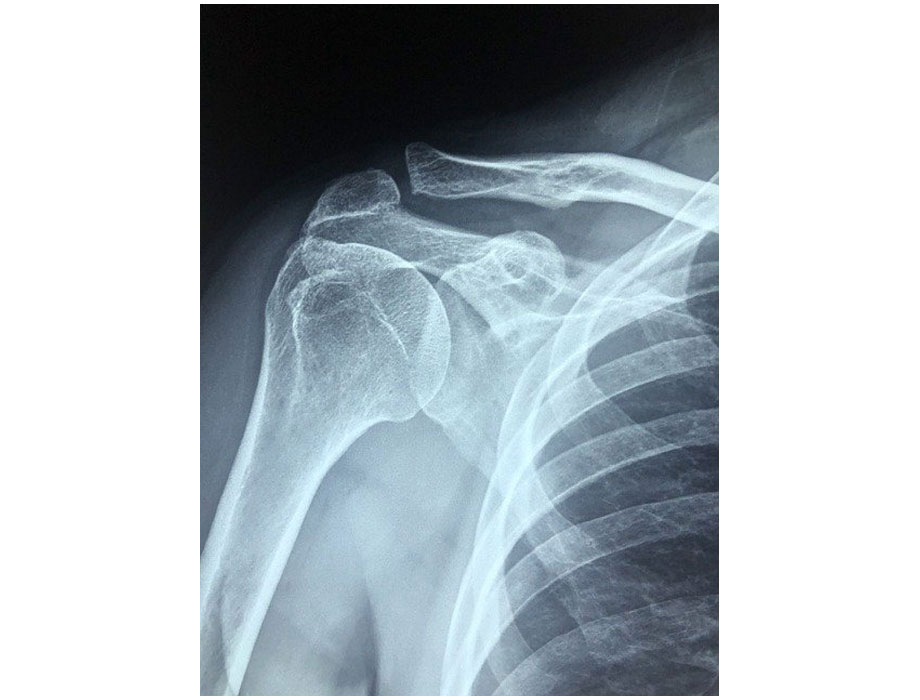

Los resultados de un análisis dirigido por investigadores del estudio de Fase 2 111-205 de BioMarin encontraron que los niños que recibieron VOXZOGO (n = 30) tuvieron aumentos significativos en la longitud del hueso y el área cortical metacarpiana después de aproximadamente cinco años de terapia, lo que sugiere que el tratamiento permitió que el hueso permaneciera fuerte a medida que se alargaba.